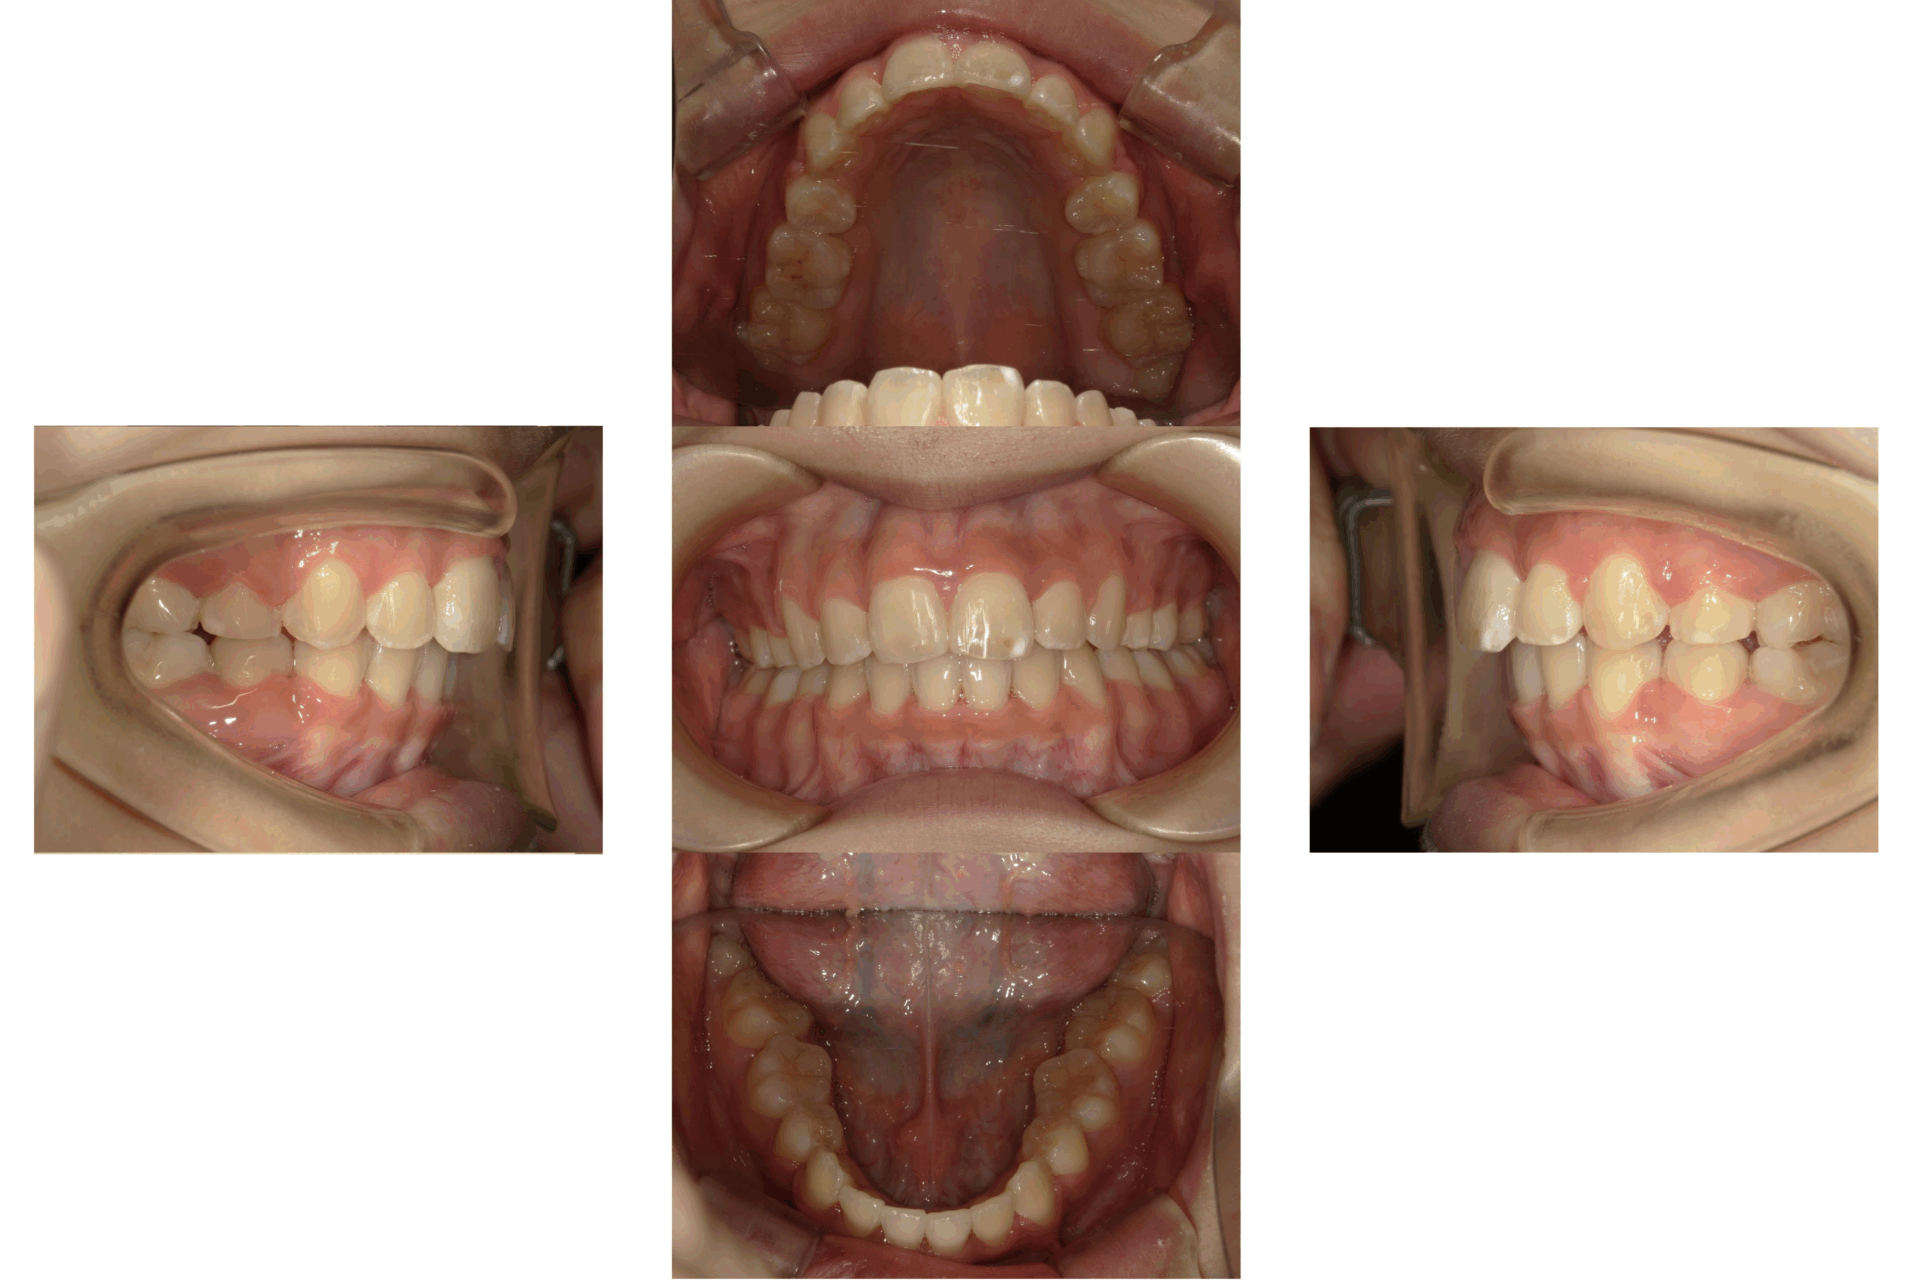

20代、女性、ワイヤー

| 施術内容 | 主訴:口ゴボが気になる。 詳細:ワイヤー矯正での歯並び改善 口元がかなり変化し、とても満足された症例です。 |

| 治療期間 | 16ヶ月(3/24現在 治療終了) |

| 費用 | ワイヤー矯正 60万円(税込660,000円) |